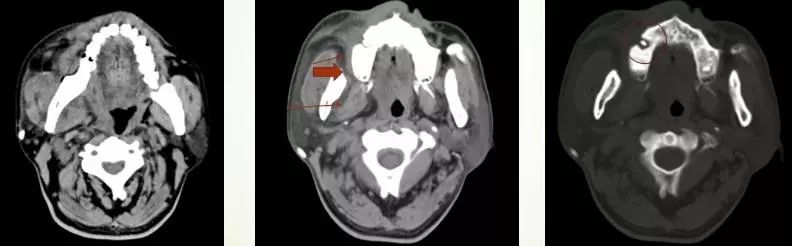

04 咀嚼肌间隙、颌下间隙、左侧颞下间隙,颊间隙,翼颌间隙

男,55岁,左下后牙反复肿疼1年余,加重1月余,疼痛剧烈伴张口受限,面部肿胀。

咀嚼肌间隙有脓肿形成。